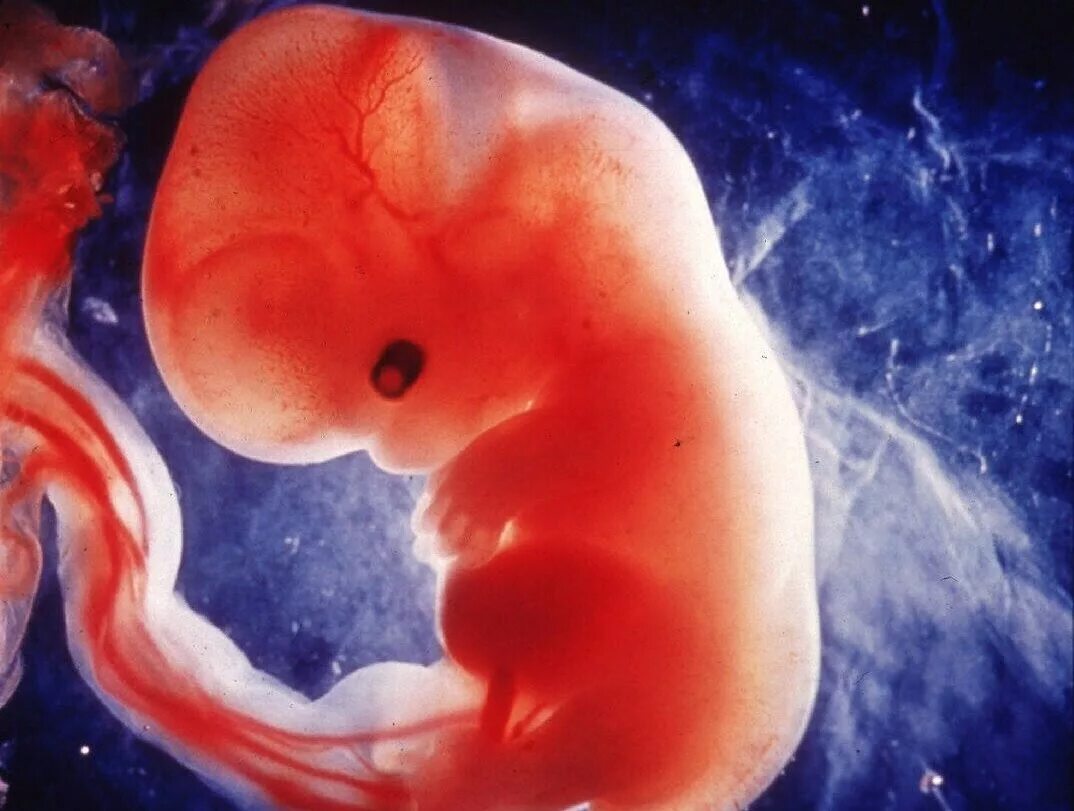

7 недель какой ребенок